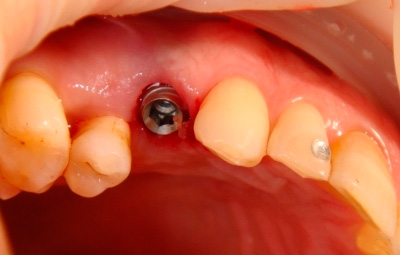

Клинический случай 3. Иммедиат имплантация с одномоментной нагрузкой первого премоляра верхней челюсти справа

Д.м.н., профессор Мушеев И.У.

Согласно показаниям, у пациентки удаляется первый премоляр на верхней челюсти справа.

Атравматичное удаление зуба, тщательный кюретаж лунки удаленного зуба.